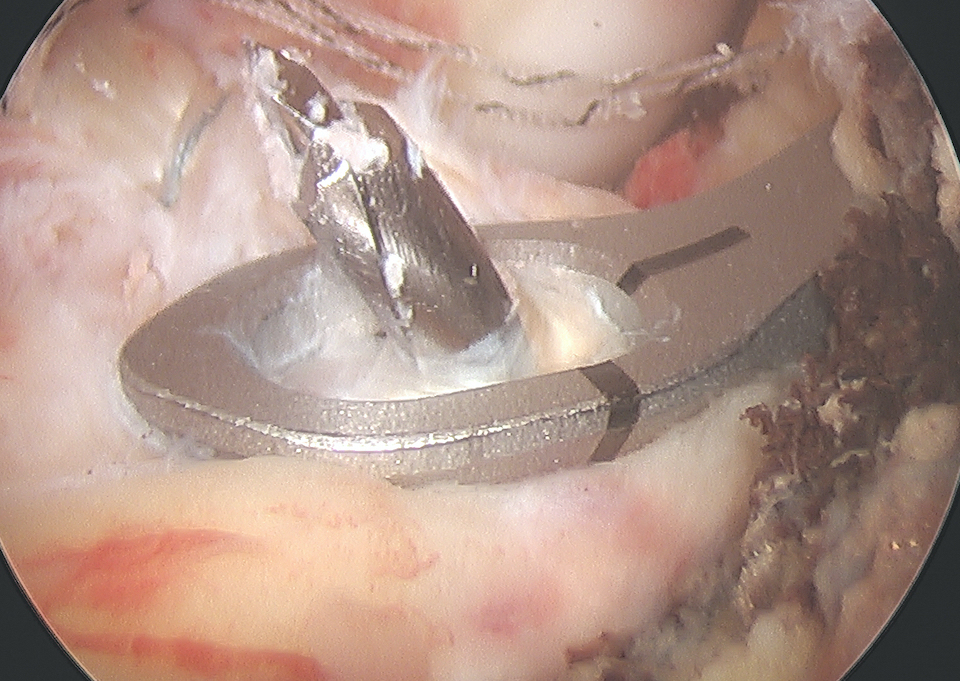

Arthroscopic suture fixation

Fragment flipped and insertion debrided Avulsion fragment reduction Passage of two loop sutures with scorpion

Reduce fragment and hold with ACL tibial guide

- medial tibial incision, pass beath pins x 2 (preferable cannulated)

- 1 cm between tunnels

- beath pins exit through bony fragment

- retrieve sutures

- reduced fragment, knee in full extension

- tie over bony bridge or over cortical button

2. Companies make cannulated beath pins, allowing suture loops to be passed up the pins